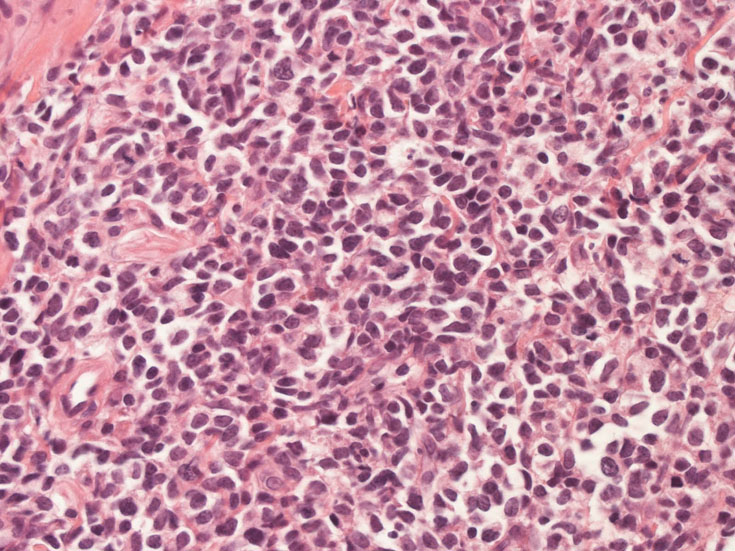

罹患リンパ節の基本構造は消失し腫瘍細胞のびまん性増殖で置換されている。非腫瘍性の小リンパ球(CD3+, CD4/8+)が濾胞様に散在して残る(Fig.01)。不整型または類円形の明るい核をもつmedium-sizeのリンパ球様細胞が密に増殖している。細胞質は乏しい(Fig.02)。CD68陽性macrophageが多く混在する部分が認められた(Fig.03)。

Fig04, Fig05は腫瘍細胞の拡大像。大型異型細胞の出現が認められる。腫瘍細胞はCD4+, CD56+, CD123+(Fig.06)

tcells02.jpg